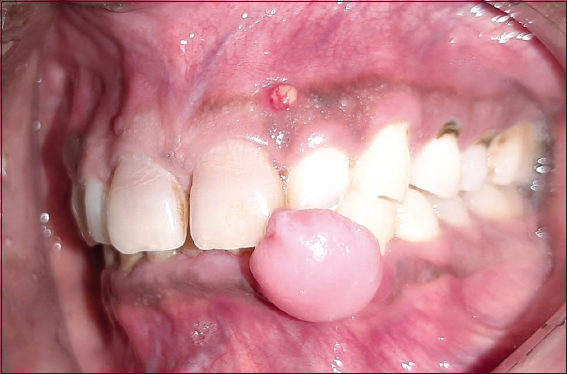

A 49-year-old man with a 4-year history was presented to the outpatient periodontics department for evaluation of a painless, slowly growing, firm gingival mass in the left lower front tooth region [Figure 1]. Its enlargement began as a small nodule and progressed till it impinged on mastication. He had no relevant medical history and was not on any medication. Intraoral examination revealed a single sessile swelling of approximately 10 mm × 7 mm that extended mesiodistally from teeth #32 to #33 and attached intraorally in the left lower gingiva [Figure 2].

Figure 1: Preoperative view

Figure 2: Extension of the swelling